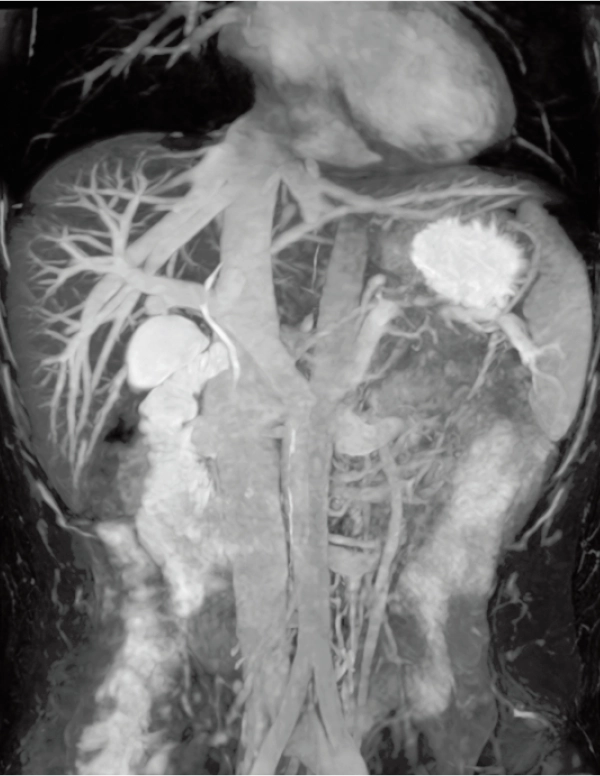

DWI AX (MIP)

3.7×3.1×5.0 mm

3st total scan time 7:25

3D MRCPA (MIP)